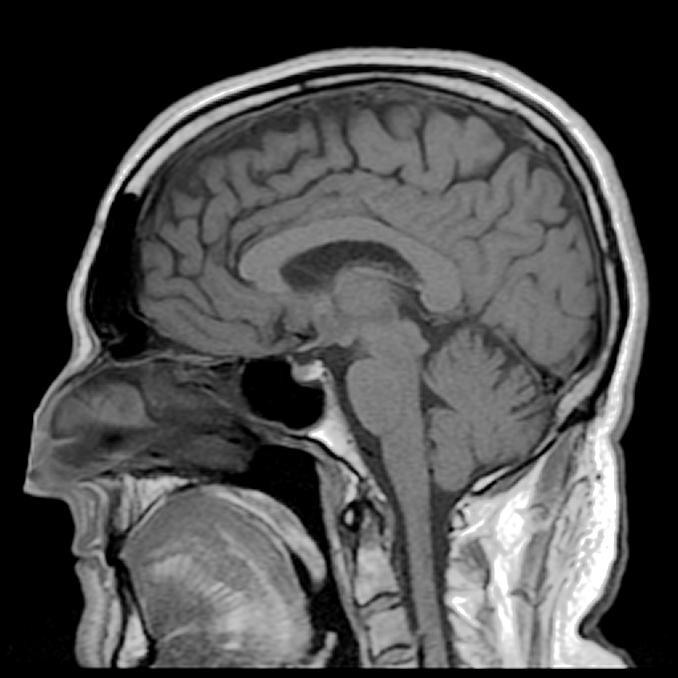

▼1985年時,Clive在一場演奏會後小睡片刻,醒來時發現兒子站在面前,但他卻想不起兒子的名字。從那一天開始,他的世界改變了。他去醫院接受檢查,確診感染單純皰疹病毒,這種病毒入侵他的大腦,損害他的神經,漸漸將他的記憶清空。